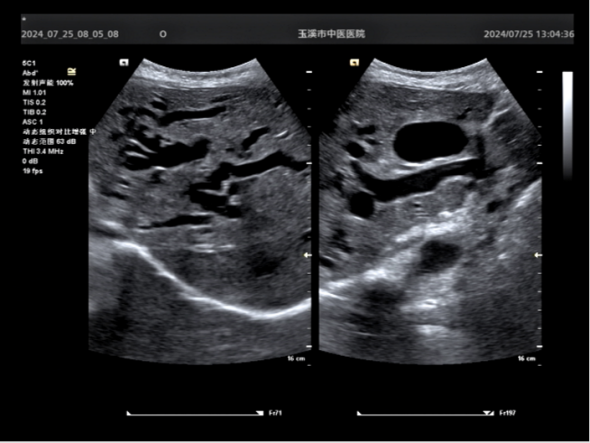

術(shù)前CT和B超顯示肝內(nèi)外膽管擴(kuò)張